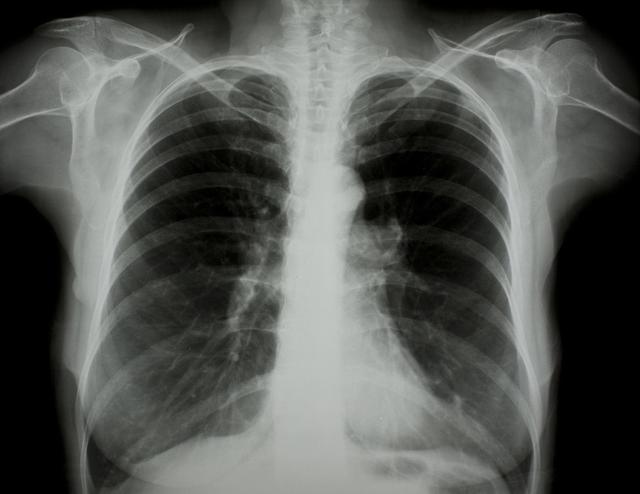

涪陵地區(qū)最新肺炎情況顯示,疫情形勢(shì)嚴(yán)峻。目前,當(dāng)?shù)卣歪t(yī)療部門正在積極應(yīng)對(duì),采取一系列措施控制疫情傳播。具體感染人數(shù)、癥狀表現(xiàn)、疫苗接種情況等仍在持續(xù)更新中。請(qǐng)廣大市民密切關(guān)注官方發(fā)布的信息,做好個(gè)人防護(hù),共同抗擊疫情。涪陵地區(qū)肺炎疫情嚴(yán)峻,政府積極應(yīng)對(duì),請(qǐng)市民關(guān)注官方信息,加強(qiáng)個(gè)人防護(hù)。

據(jù)最新官方數(shù)據(jù)顯示,涪陵地區(qū)肺炎病例數(shù)量令人擔(dān)憂,截至目前,涪陵地區(qū)累計(jì)確診肺炎病例XX例,疑似病例XX例,請(qǐng)大家務(wù)必提高警惕,不可掉以輕心。